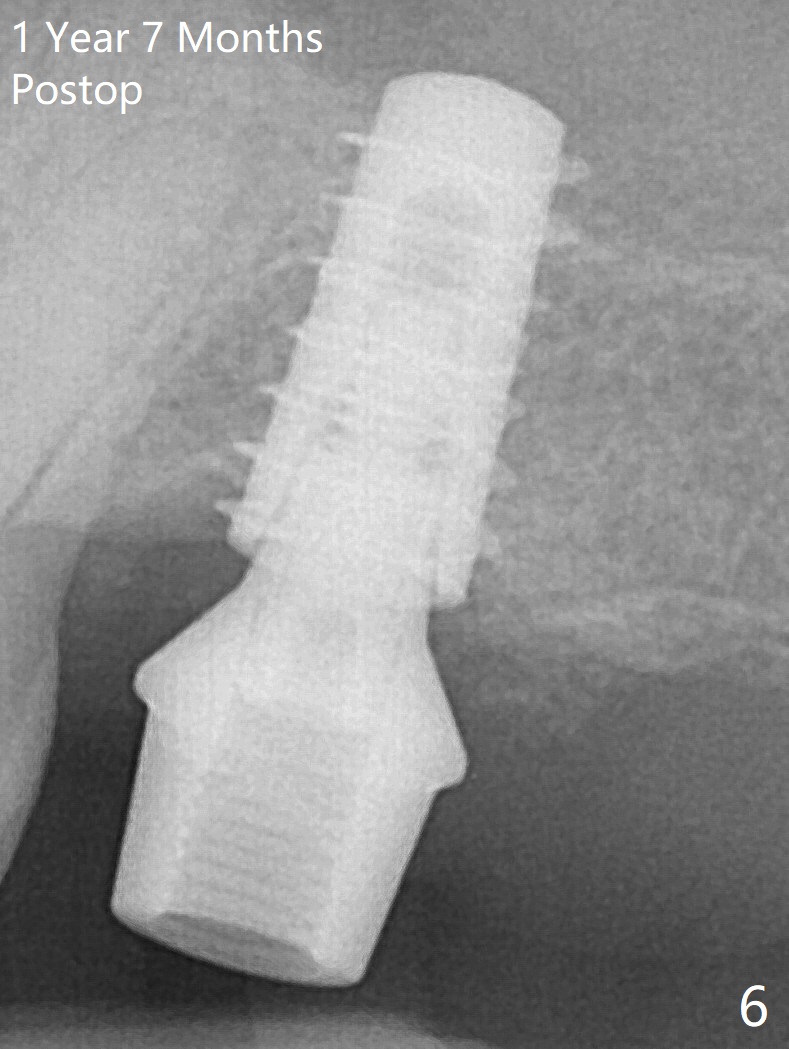

The 3 remaining sockets (Fig.1 *) around the final implant are filled with sticky bone (Fig.2 *).  The sockets are non-existing 1 year 7 months and 8 months postop (Fig.6,7 (BW)).